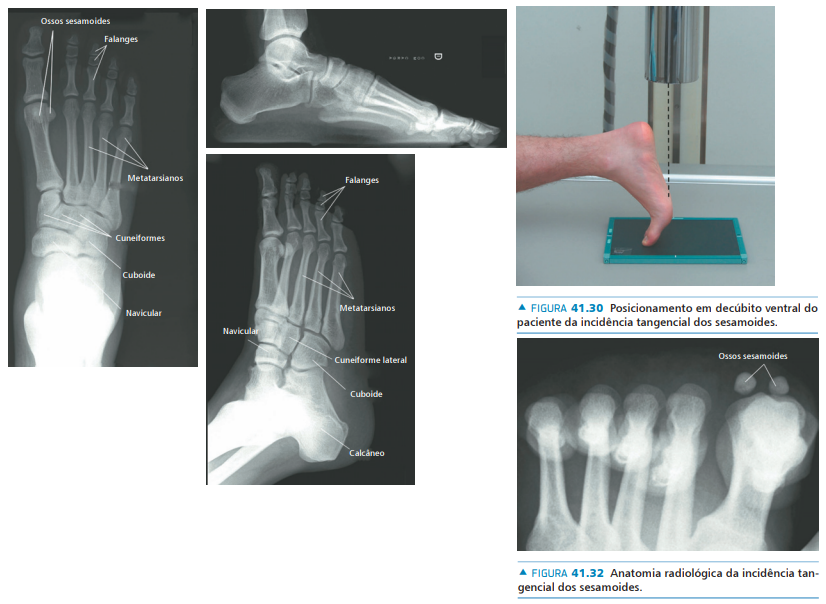

• Na avaliação radiográfica, quais incidências solicitar?

A

• AP com carga

• Perfil com carga

• Oblíqua

• Axial dos sesamóides